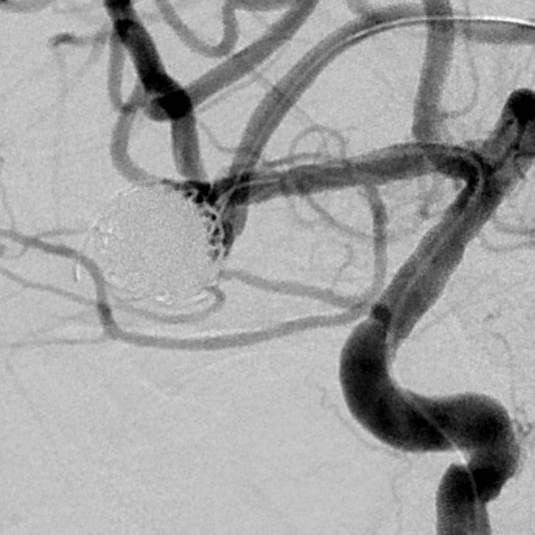

粗大分支从破裂瘤体上发出来,急性期能单纯致密栓塞吗?

病史:中年女性,新冠感染,颅内动脉瘤破裂,Hunt-Hess 4级

最终,动脉瘤瘤体致密栓塞,各个分支保留良好